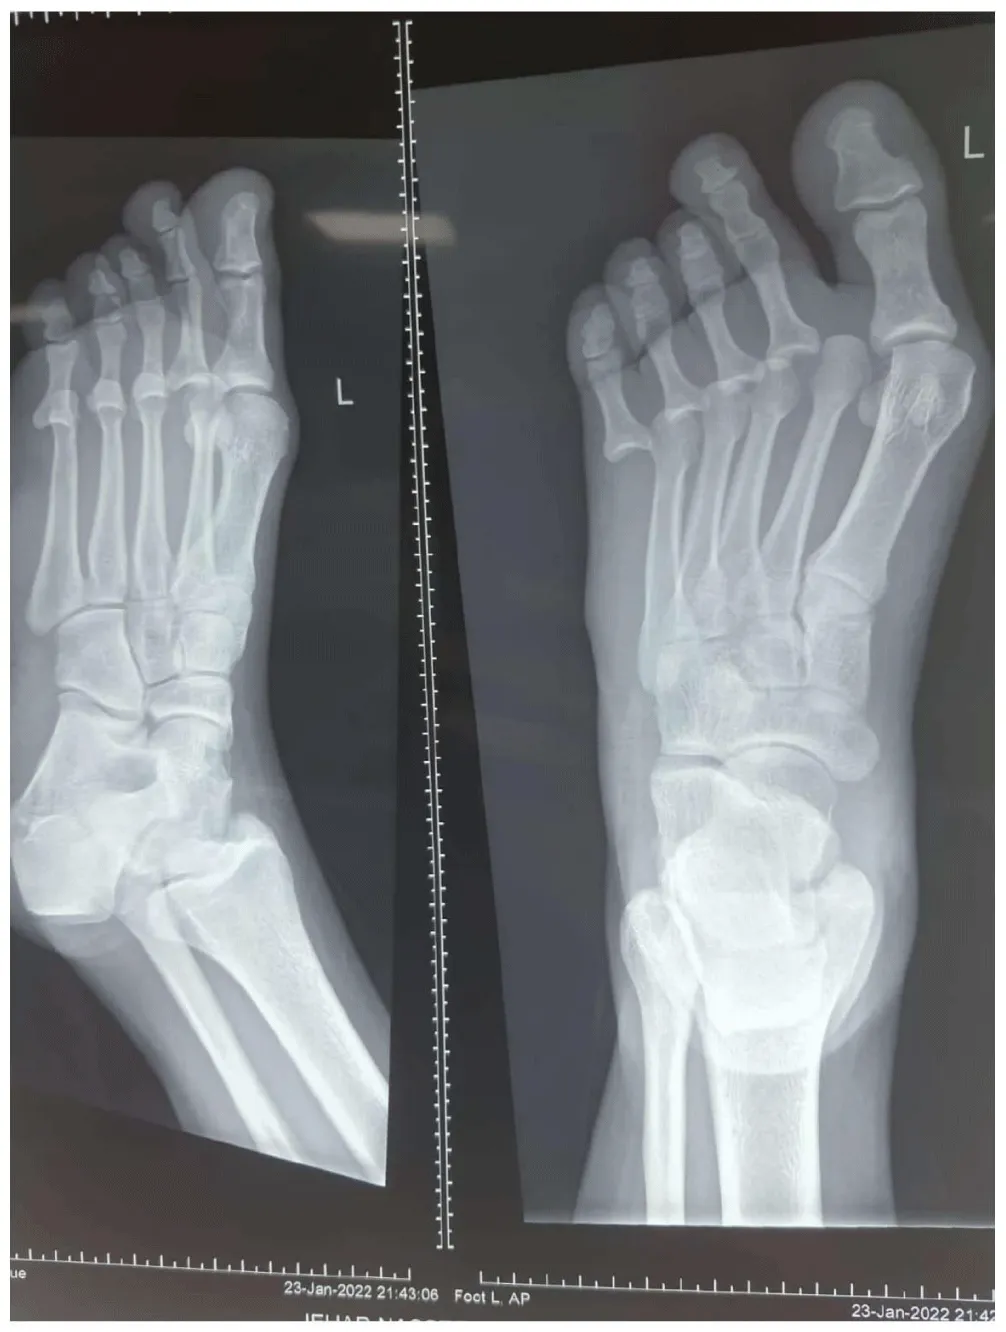

The patient was admitted and, after a preliminary workup, was scheduled for closed / open reduction under anesthesia. He underwent closed manipulation and reduction under General anesthesia by simultaneous reverse mode of injury manipulation of all four toes to free any soft tissue impingement. The joints were stable and congruent after closed reduction without any need for K-wire stabilization (Figure 2). Post buddy toe operatively strapping with below-knee plaster of Paris posterior back slab was applied for immobilization of the foot in neutral position. Patient was kept non-weight bearing for 05 weeks, followed by progressive weight bearing as tolerated.At 12 weeks (Figure 3), follow up patient was doing fine with full weight bearing and had returned to pre-injury level activities with good painless range of toe movements. The patient was followed for a period of 06 months post-injury without any complaints.